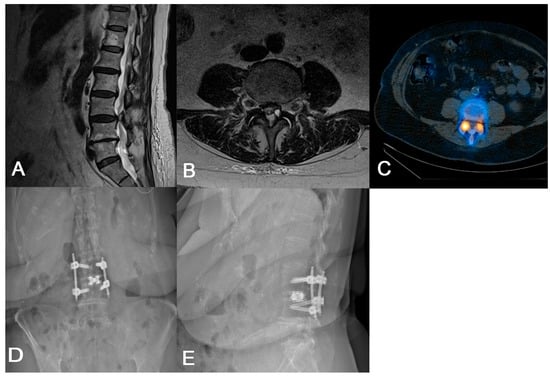

3.3. Measuring Kambin’s Triangle